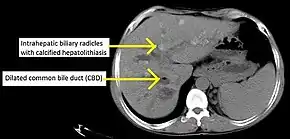

![]() | |

| Cholangiogram of primary sclerosing cholangitis. | |

Historically, a cholangiogram would be obtained via endoscopic retrograde cholangiopancreatography (ERCP), which typically reveals "beading" (alternating strictures and dilation) of the bile ducts inside and/or outside the liver. Currently, the preferred option for diagnostic cholangiography, given its non-invasive yet highly accurate nature, is magnetic resonance cholangiopancreatography (MRCP), a magnetic resonance imaging technique. MRCP has unique strengths, including high spatial resolution, and can even be used to visualize the biliary tract of small animal models of PSC.[18]